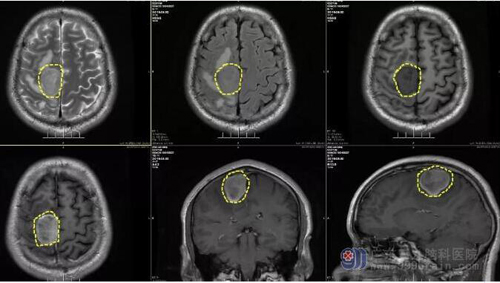

图1:术前MR示右侧顶部镰旁示一团块状占位性病变,呈稍长T1稍长T2异常信号影,FLAIR序列呈稍高信号影,DWI序列呈稍高信号,ADC图呈稍低信号影,其ADC值为(0.834±0.031)×10-3mm2/s;增强后病变明显欠均匀强化,范围约为3.5cm×2.8cm×3.7cm,周围示片状长T1长T2水肿信号影